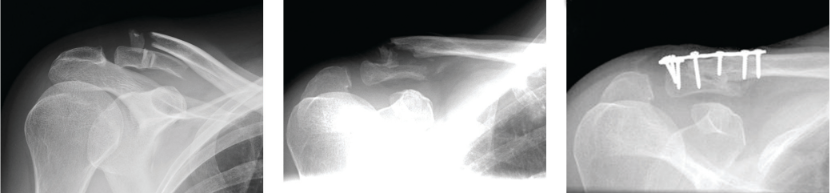

对于不稳定性骨折,手术治疗效果优于保守治疗。下面以图片的形式展示不同的固定方法。

锁骨远端锁定钢板固定